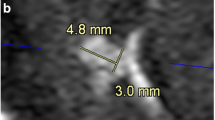

Lengths were statistically higher in CS TOF than in conventional TOF (left: 55.4 ± 4.2 vs. 51.3 ± 5.0, p < 0.001, ICC = 0.868; right: 55.5 ± 4.4 vs. 51.1 ± 4.5, p < 0.001, ICC = 0.876). The distance was also statistically higher in CS TOF than in conventional TOF (left: 42.6 ± 4.6 vs. 39.5 ± 5.1, p < 0.001, ICC = 0.916; right: 40.7 ± 3.6 vs. 37.8 ± 3.9, p < 0.001, ICC = 0.913). This result demonstrated that the vasculature visible using CS TOF was significantly longer than that of conventional TOF (Fig. 4).

Bland-Altman plots represent the differences in (a) lengths and (b) distance measured in the predominant vascular trees of CS TOF and TOF in the right and left hemispheres (RH/LH). CS TOF shows longer LSA vasculature in both length and distance. CS, compressed sensing; LSA, lenticulostriate artery; TOF, time-of-flight